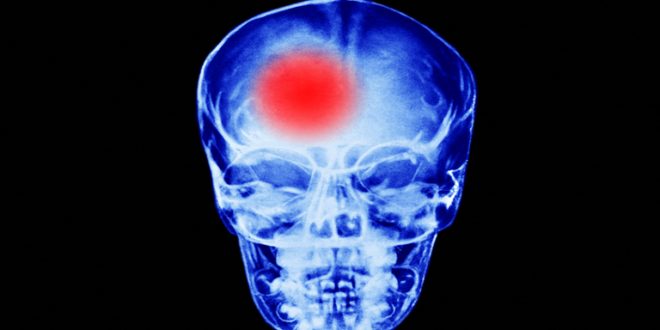

تعد السكتة الدماغية سببا رئيسيا للوفاة والعجز في جميع أنحاء العالم ، لكن الخبراء يصرون على أن الحالة يمكن الوقاية منها.

وتوضح عيادة كليفلاند أنه عندما تحدث السكتة الدماغية بعد تناول مشروب الطاقة، فإنها تكون نتيجة متلازمة تضيق الأوعية الدماغية الانعكاسية (RCVS).

ويتسبب هذا في حدوث تشنج مفاجئ في الأوعية الدموية في الدماغ، والذي يمكن أن يؤدي إما إلى تقييد تدفق الدم إلى العضو أو التسبب في حدوث نزيف. وأهم أعراض RCVS التي يتم اكتشافها هي صداع مفاجئ، والذي يشتد بسرعة في غضون بضع دقائق.